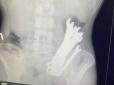

Лікарі в Черкасах дістали з тіла пацієнта... шість гайкових ключів (фото)

Медики повідомили, що незвичайний випадок стався минулого місяця. Пацієнта госпіталізували з флегмоною шиї, розривом стравоходу на рівні глотки та середньої третини, тотальним медіастинітом, емпіємою плеври з правого боку, сторонніми тілами та опущення...